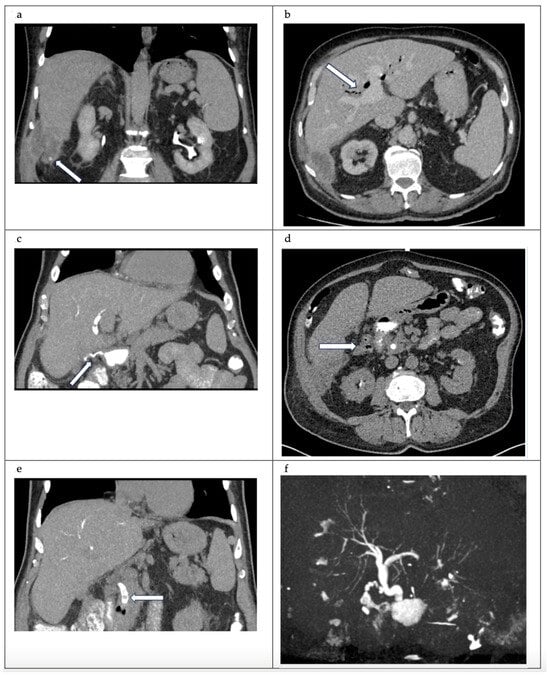

An MRCP would be an alternative to a CT cholangiogram., in our case, however, MRCP was not available on short notice. The parahepatic collection and extensive pneumobilia were once again noted (Figure 1a,b). Four filling defects in the common bile duct were discovered, with the largest measuring 5 mm (Figure 1d). A gas-containing collection inferior to the cystic duct clips was identified with biliscopin extravasation into the collection and duodenum, which is representative of cystic duct remnant–duodenal fistula (Figure 1c,d). A 3D reconstruction image helps to visualise the anatomy of the biliary system (Figure 1f and Figure 2).

Figure 1.

(a) Coronal view CT abdomen. Porto-venous phase. Adjacent to segment 6 of the liver, there is a 14.4 × 4.9 × 6 cm collection (white arrow). The collection has a mildly thickened wall. The collection contains multiple dependent calculi. (b) Axial view CT abdomen. Porto-venous phase. Marked pneumobilia (white arrow). (c) Coronal view CT cholangiogram. Contrast leak from the cystic stump into duodenum (white arrow). (d) Axial view CT cholangiogram—post-biliscopin phase. A lobulated and gas-containing outpouching immediately superior to the cholecystectomy clip, that communicated with the cystic duct, as well as a fistulous tract with the first part of the duodenum—representative of a fistula (white arrow outlines the collection). (e) Coronal view CT cholangiogram. 5 mm filling defect at the distal common bile duct (CBD) (white arrow) (f) 3D reconstructed model.